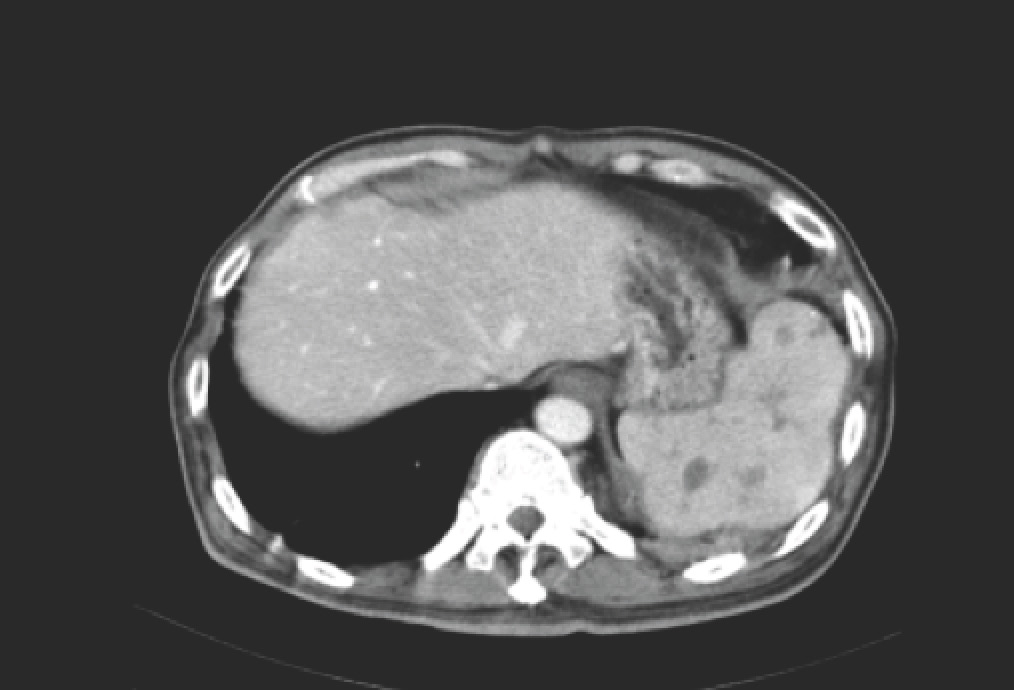

A middle-aged (60-year-old) man with Type 2 diabetes mellitus and past history of tuberculosis presented with low-grade fever for 2 weeks and a 1.5 cm nodule over his left lower back (approximately L1 level). This was determined to be an abscess and creamy white pus was aspirated by his general practitioner. The Gram stain showed Gram-negative bacilli, and his chest X-ray (and a segment of the subsequent CT abdomen) is shown below.

The CT abdomen shows an irregular spleen with multiple hypodense lesions. In this context, it represents splenic abscesses. The chest X-ray shows blunting of the left costophrenic angle, representing a pleural effusion. The lower back nodule represents an abscess – in this case linked by a sinus tract to the spleen. Taking everything into consideration – Gram-negative bacteria, patient with diabetes mellitus, splenic abscesses, tropical country – the Gram-negative bacteria is almost invariably going to be Burkholderia pseudomallei, the causative agent of melioidosis. There are two key review papers – the first published in 2005 in Clinical Microbiology Reviews, and the second (behind a pay wall) published in 2012 in the New England Journal of Medicine. Current treatment protocols involve prescription of intravenous ceftazidime for 2 weeks followed by a prolonged course of oral trimethoprim/sulfamethoxazole +/- doxycycline.